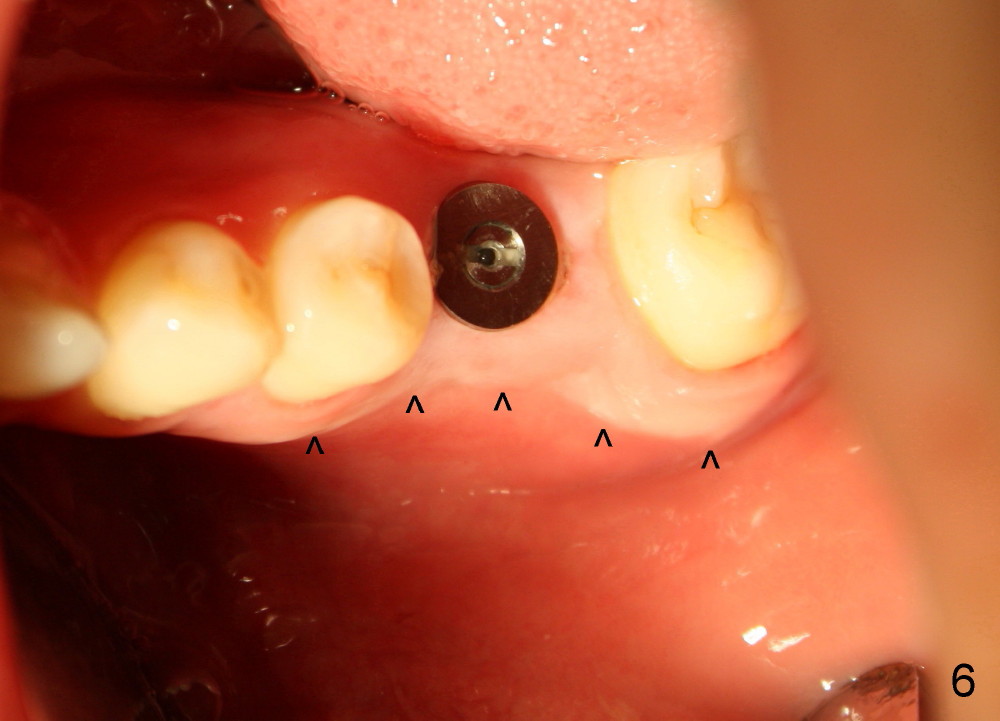

小张,男,22岁,大学刚毕业,忙于找工作,治疗不够积极,左下第一磨牙根管治疗失败,根尖,根分叉阴影(图一*),好像即刻植牙不太合适,建议拔牙后四周,六周之间回来植牙。但是他很拖拉,三个月才回来让我们看看,骨头似乎愈合不错(图二),他又消失五个月,最后还是登门,骨质仿佛继续形成(图三),植入六乘十七毫米植牙(图四,五),舌侧牙龈马上形成cuff(图五**),好像attached gingiva,与邻牙一致(箭头)。您能猜为什么植牙舌侧形成牙龈cuff?

图六是术后十天拍摄,它显示颊侧骨板明显萎缩(箭头),这可能拔牙后形成。由于颊侧骨板萎缩,植牙偏向舌侧,给舌侧牙龈施加压力,便形成牙龈cuff。